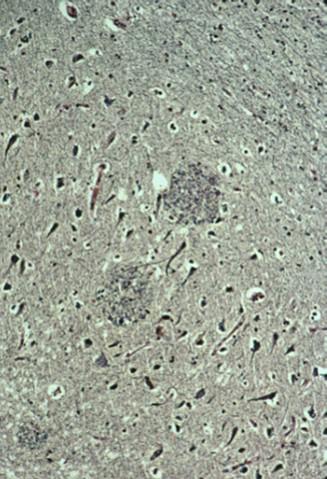

what is this a dead giveaway of

spongiform (prion disease)

what happens in CJD

rapidly progressive dementia

cerebelar ataxia

what is affected in CJD

grey matter